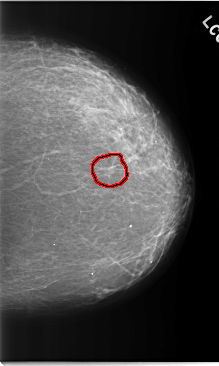

C_0205_1.LEFT_MLO

LEFT_MLO LINES 5896 PIXELS_PER_LINE 4072 BITS_PER_PIXEL 12 RESOLUTION 50 OVERLAY

FILE: C_0205_1.LEFT_MLO.OVERLAY

TOTAL_ABNORMALITIES 1

ABNORMALITY 1

LESION_TYPE MASS SHAPE IRREGULAR MARGINS ILL_DEFINED

ASSESSMENT 4

SUBTLETY 2

PATHOLOGY MALIGNANT

TOTAL_OUTLINES 1

BOUNDARY